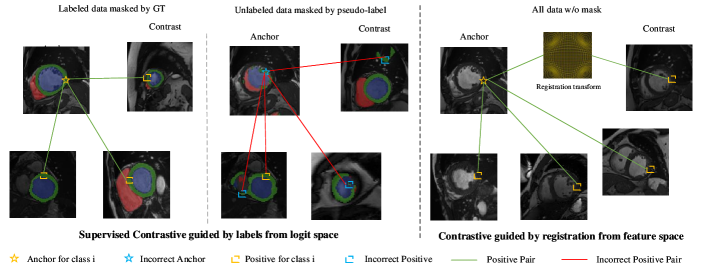

3.4 Registration-enhanced positive sampling

We next show how to use registration to improve the supervised contrastive learning loss in Eq. 4. Fig. 2 shows the shortcomings of standard positive sampling in comparison to our novel approach integrating registration. Positives derived from (pseudo-)labels are sampled from any location within the same organ or class as shown in Eq. 4. In contrast, registration-based positives correspond to the exact same anatomical location within the organ, albeit in different volumes or patients. Any noise in registration-based positives stems from registration inaccuracies and is independent of pseudo-label errors. Therefore, we augment the set of positive samples by incorporating registration-based examples. This approach reduces the confirmation bias that can arise when learning only from pseudo-labels.